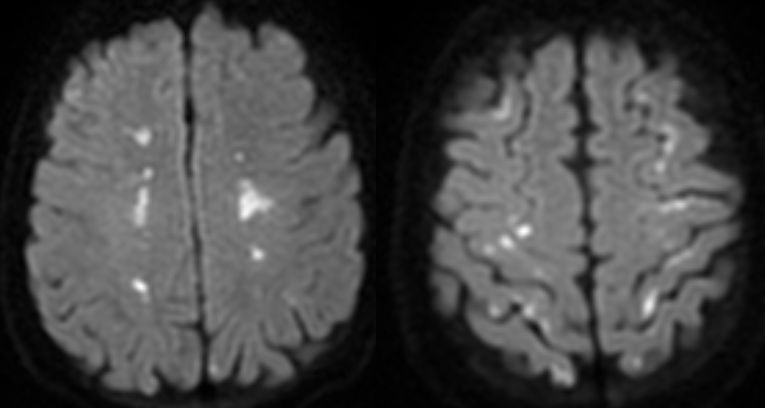

患者30岁,女性,头痛6天。既往类固醇类药物治疗Kikuchi’s 病史,患者入院后胸部CT证实肺结核。脑脊液细菌、分枝杆菌和真菌染色和培养结果均为阴性,但脑脊液结核分枝杆菌聚合酶链反应(PCR)呈阳性,确诊结核性脑膜脑炎。患者在开始使用地塞米松、利福平、乙胺丁醇、异烟肼、吡嗪酰胺和莫西沙星治疗后病情好转。两周后出院,除了轻微头痛,全部症状消失。依次为轴位DWI,FLAIR和钆增强T1加权图像。A-C:初始发病时显示弥漫性软脑膜增强。D-F:抗结核药物治疗后5周出现严重头痛时的随访影像,显示左侧脉络丛炎。G-I:第6个月的随访图像,显示病变明显改善。

答案:矛盾反应。

结核病患者在开始治疗后,临床或放射学上原有病变的恶化或出现了新病变被称为矛盾反应(paradoxical reaction,PXR)。由于PXR可能被误诊为耐药状态或治疗失败,导致结核病的治疗混乱。这个病例的PXR表现为脉络丛炎,在此,期望临床医师提高对这种情况的认识。PXR与宿主免疫应答反应、分枝杆菌产物直接作用有关。

TB得到有效治疗后,结核菌被迅速杀灭后释放大量结核蛋白和胞壁产物,这些蛋白、磷脂、多糖引发超敏反应,出现局部毛细血管扩张、炎性细胞渗出、聚集,进而造成原本不活跃的结核病灶扩大,从而出现相应的临床或影像表现。神经影像学表现包括基底渗出物增加,新发的或恶化的结核瘤以及视神经炎或脊髓炎。渗出严重可以影响阻塞脑脊液回流,导致颅内压升高,以及脊髓疾病,甚至可以以尿潴留为首发症状。矛盾反应危及生命或致残时,需要使用高剂量的糖皮质激素等免疫调节药物治疗。